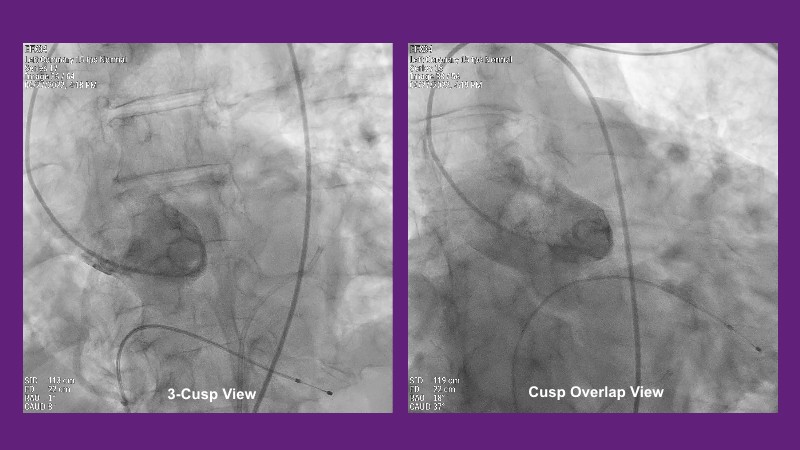

Don’t miss this PCR Tokyo Valves 2025 session replay, where leading experts share key techniques for simplifying and optimising TAVI procedures with the Evolut device. This session covers essential insights into safely performing procedures on patients with various anatomical types using the self-expandable valve, while emphasising the importance of long-term patient care and outcomes. Discover valuable strategies for surgical explantation of transcatheter aortic bioprostheses, coronary cannulation, and commissural alignment post-TAVR. Learn expert tips for streamlining procedures, such as semi-rapid pacing, using Dryseal long, and skipping pre-BAV to improve TAVI results. Watch now to stay ahead in the field!